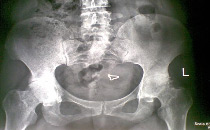

髋关节

例子

病症描述:类风湿性关节炎也可以发生于髋关节,大多数为对称性。约45%的类风湿性关节炎患者髓关节可以发病。可以表现为"晨僵"、关节疼痛、低热等症状。日久可以导致髋关节畸形、僵硬、旋转和外展障碍伴疼痛等症状。